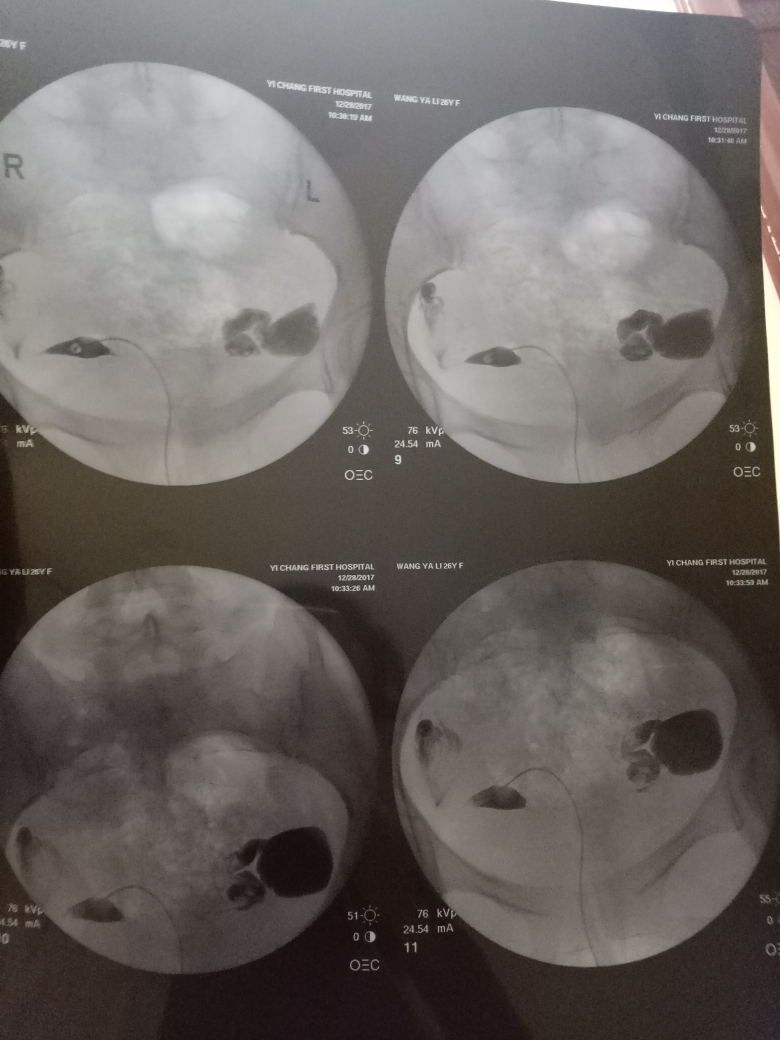

在現(xiàn)代醫(yī)學(xué)中,造影技術(shù)廣泛應(yīng)用于臨床診斷,對于不孕癥的診斷和治療也起到了重要作用,造影是一種通過放射線、超聲波等影像技術(shù)觀察人體內(nèi)部結(jié)構(gòu)和狀況的方法,完成造影后的第二個月,很多夫婦關(guān)心是否容易懷孕,造影本身并不會直接影響懷孕,但了解身體情況后,有針對性地進(jìn)行治療和調(diào)理,確實(shí)有助于提高懷孕的幾率。

通過造影技術(shù),醫(yī)生可以清晰地觀察到子宮內(nèi)部環(huán)境,如子宮內(nèi)膜厚度、輸卵管通暢情況等,若子宮環(huán)境良好,第二個月懷孕的機(jī)會將大大增加。

造影技術(shù)還可以評估卵巢功能,如卵泡數(shù)量、質(zhì)量等,若卵巢功能正常,有助于排卵和激素分泌,從而提高懷孕幾率。